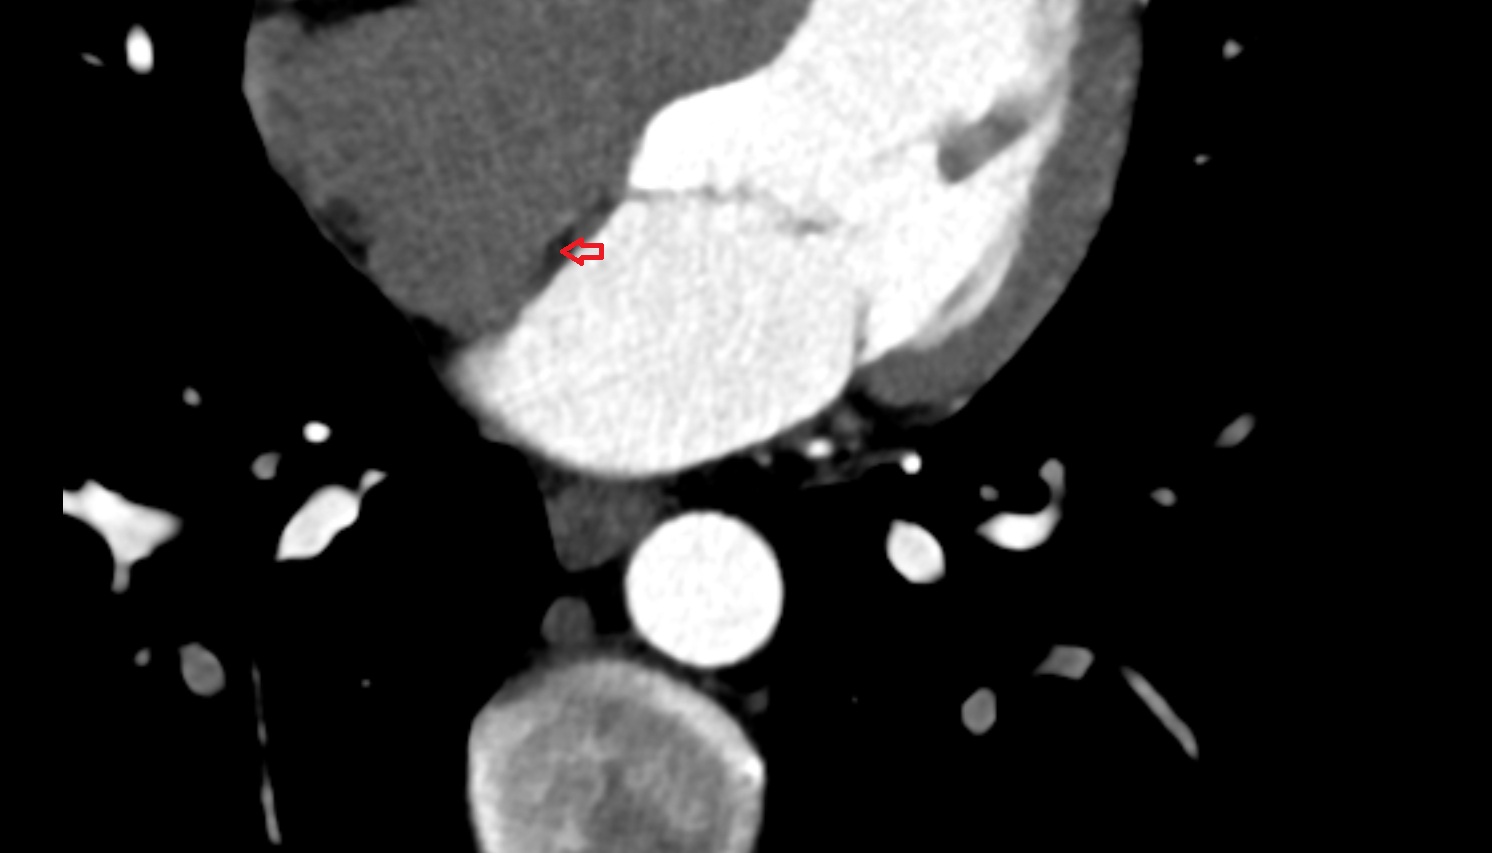

- Heart

- Left ventricle

- Right atrium

- Left atrium

- Right ventricle

- Interventricular Septum

- Left atrioventricular valve (mitral or bicuspid valve)

- Right atrioventricular valve (tricuspid valve)

- Aortic root

- Ascending aorta